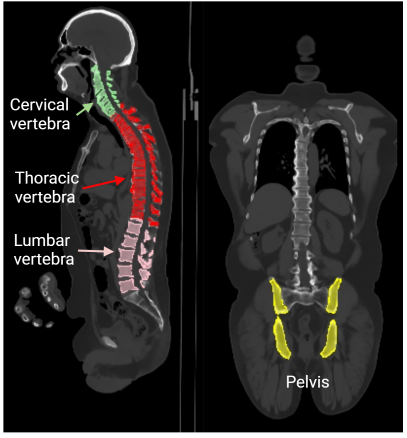

The cervical vertebra (CV: C1-C7), thoracic vertebra (TV: T1-T12), lumbar vertebra (LV: L1-L5), and pelvis regions were first segmented using the TotalSegmentor toolbox [32] installed in 3D Slicer [33], as shown in Fig. 3a. Fig. 3b further presents the manual delineation for all regions of interest (ROIs) based on the auto-segmentation results by aligning the CT, dynamic PET, and last 5-minute static PET images. The four averaged regions comprised CV from seven ROIs, TV from twelve ROIs, LV from five ROIs, and pelvis from four ROIs, which were used to extract the global bone marrow TACs from the dynamic images with lower noise. An additional ROI was placed in the descending aorta region to extract the image-derived input function by considering early and late frames simultaneously. The SUV was calculated using the data of last 5 minutes (i.e. 55-60 min).

Refer to caption

(a)

(b)

Figure 3: Illustration of bone marrow ROI placement. (a) Automatic segmentation of spine and pelvis regions enabled by TotalSegmentator. (b) Manual ROI delineation based on (a). CT HU window: [-300, 1200]